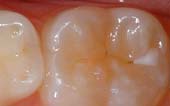

Seal Out Decay

A sealant is a protective coating that is applied to the chewing surfaces (grooves) of the back teeth (premolars and molars), where four out of five cavities in children are found. This sealant acts as a barrier to food, plaque and acid, thus protecting the decay-prone areas of the teeth.

|

Before

Sealant Applied

After